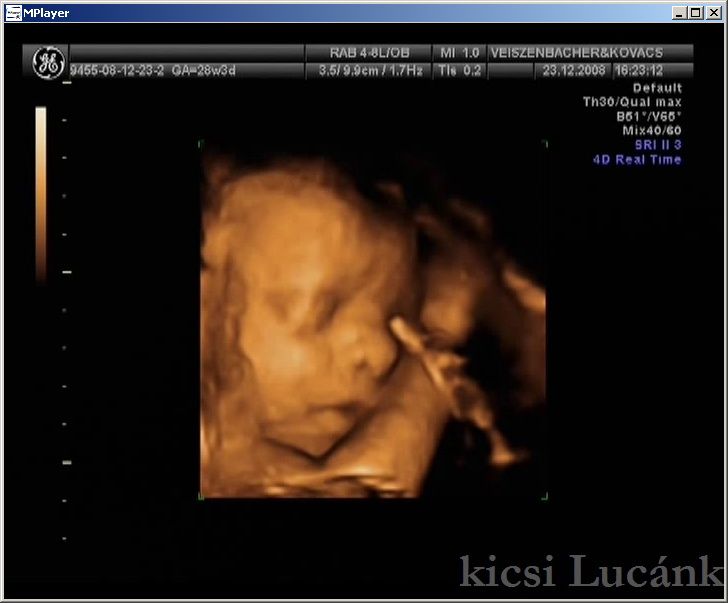

kicsi Lucánk - 2008.12.23 (3 of 13)

luca03